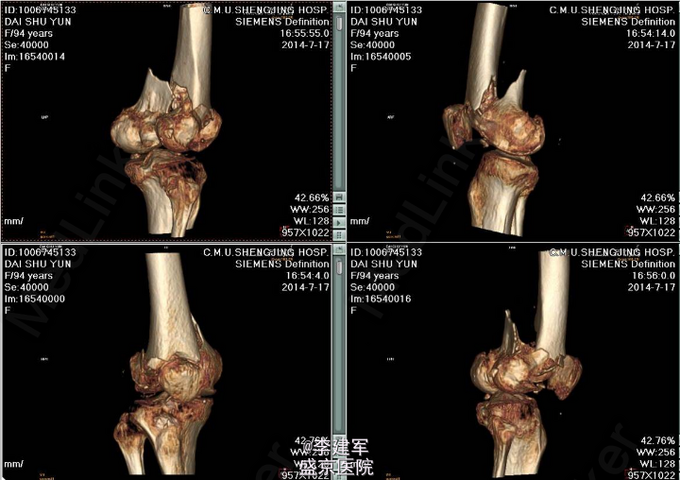

右股骨髁上粉碎性骨折 患者高龄,完善心电图,肺部CT,生化检查等,查无手术禁忌症。择期手术治疗。 手术拟行右股骨髁上粉碎性骨折闭合复位内固定术。 决定使用Liss钢板

患者高龄选用Liss钢板做闭合复位,减小手术创口。